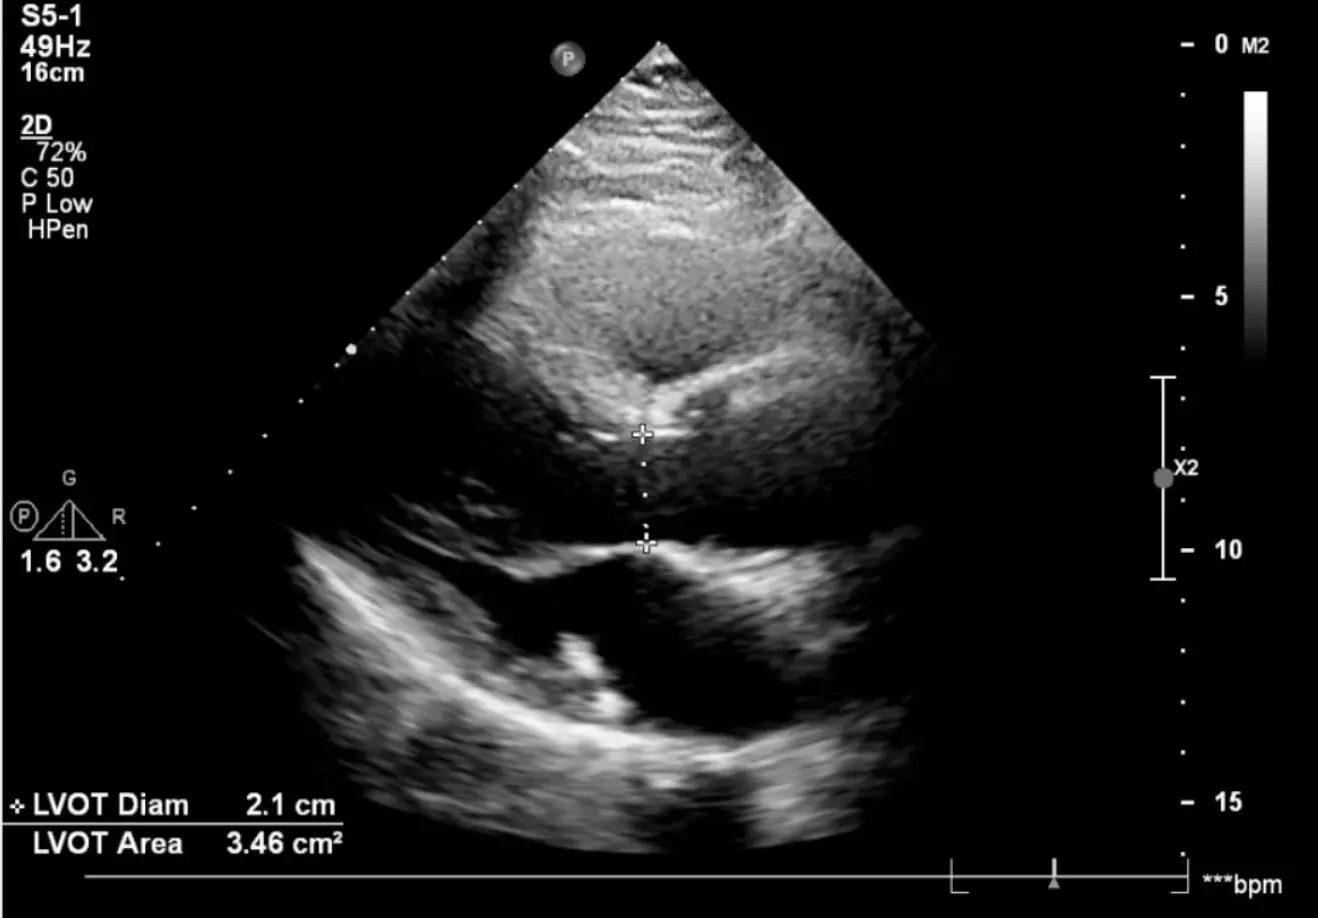

📐 Medida do Diâmetro da VSVE

• Janela: Paraesternal longitudinal com ZOOM na região da válvula aórtica

• Momento: Medir em mesossístole (abertura máxima dos folhetos aórticos)

• Local: Imediatamente abaixo (proximal) da inserção dos folhetos aórticos, na via de saída do VE

• Técnica: Medir de borda interna a borda interna (inner edge to inner edge)

• Valores normais: 1.8 - 2.4 cm (pode variar com biotipo)

⚠️ ATENÇÃO: Esta é a medida mais crítica! O diâmetro é elevado ao quadrado no cálculo da área. Erro de 1-2mm pode gerar variação significativa no Volume Sistólico e Débito Cardíaco.

💡 Dica: Use sempre ZOOM e otimize o ganho. Faça a média de 3 medidas para maior precisão. Em pacientes obesos, considere o transesofágico.